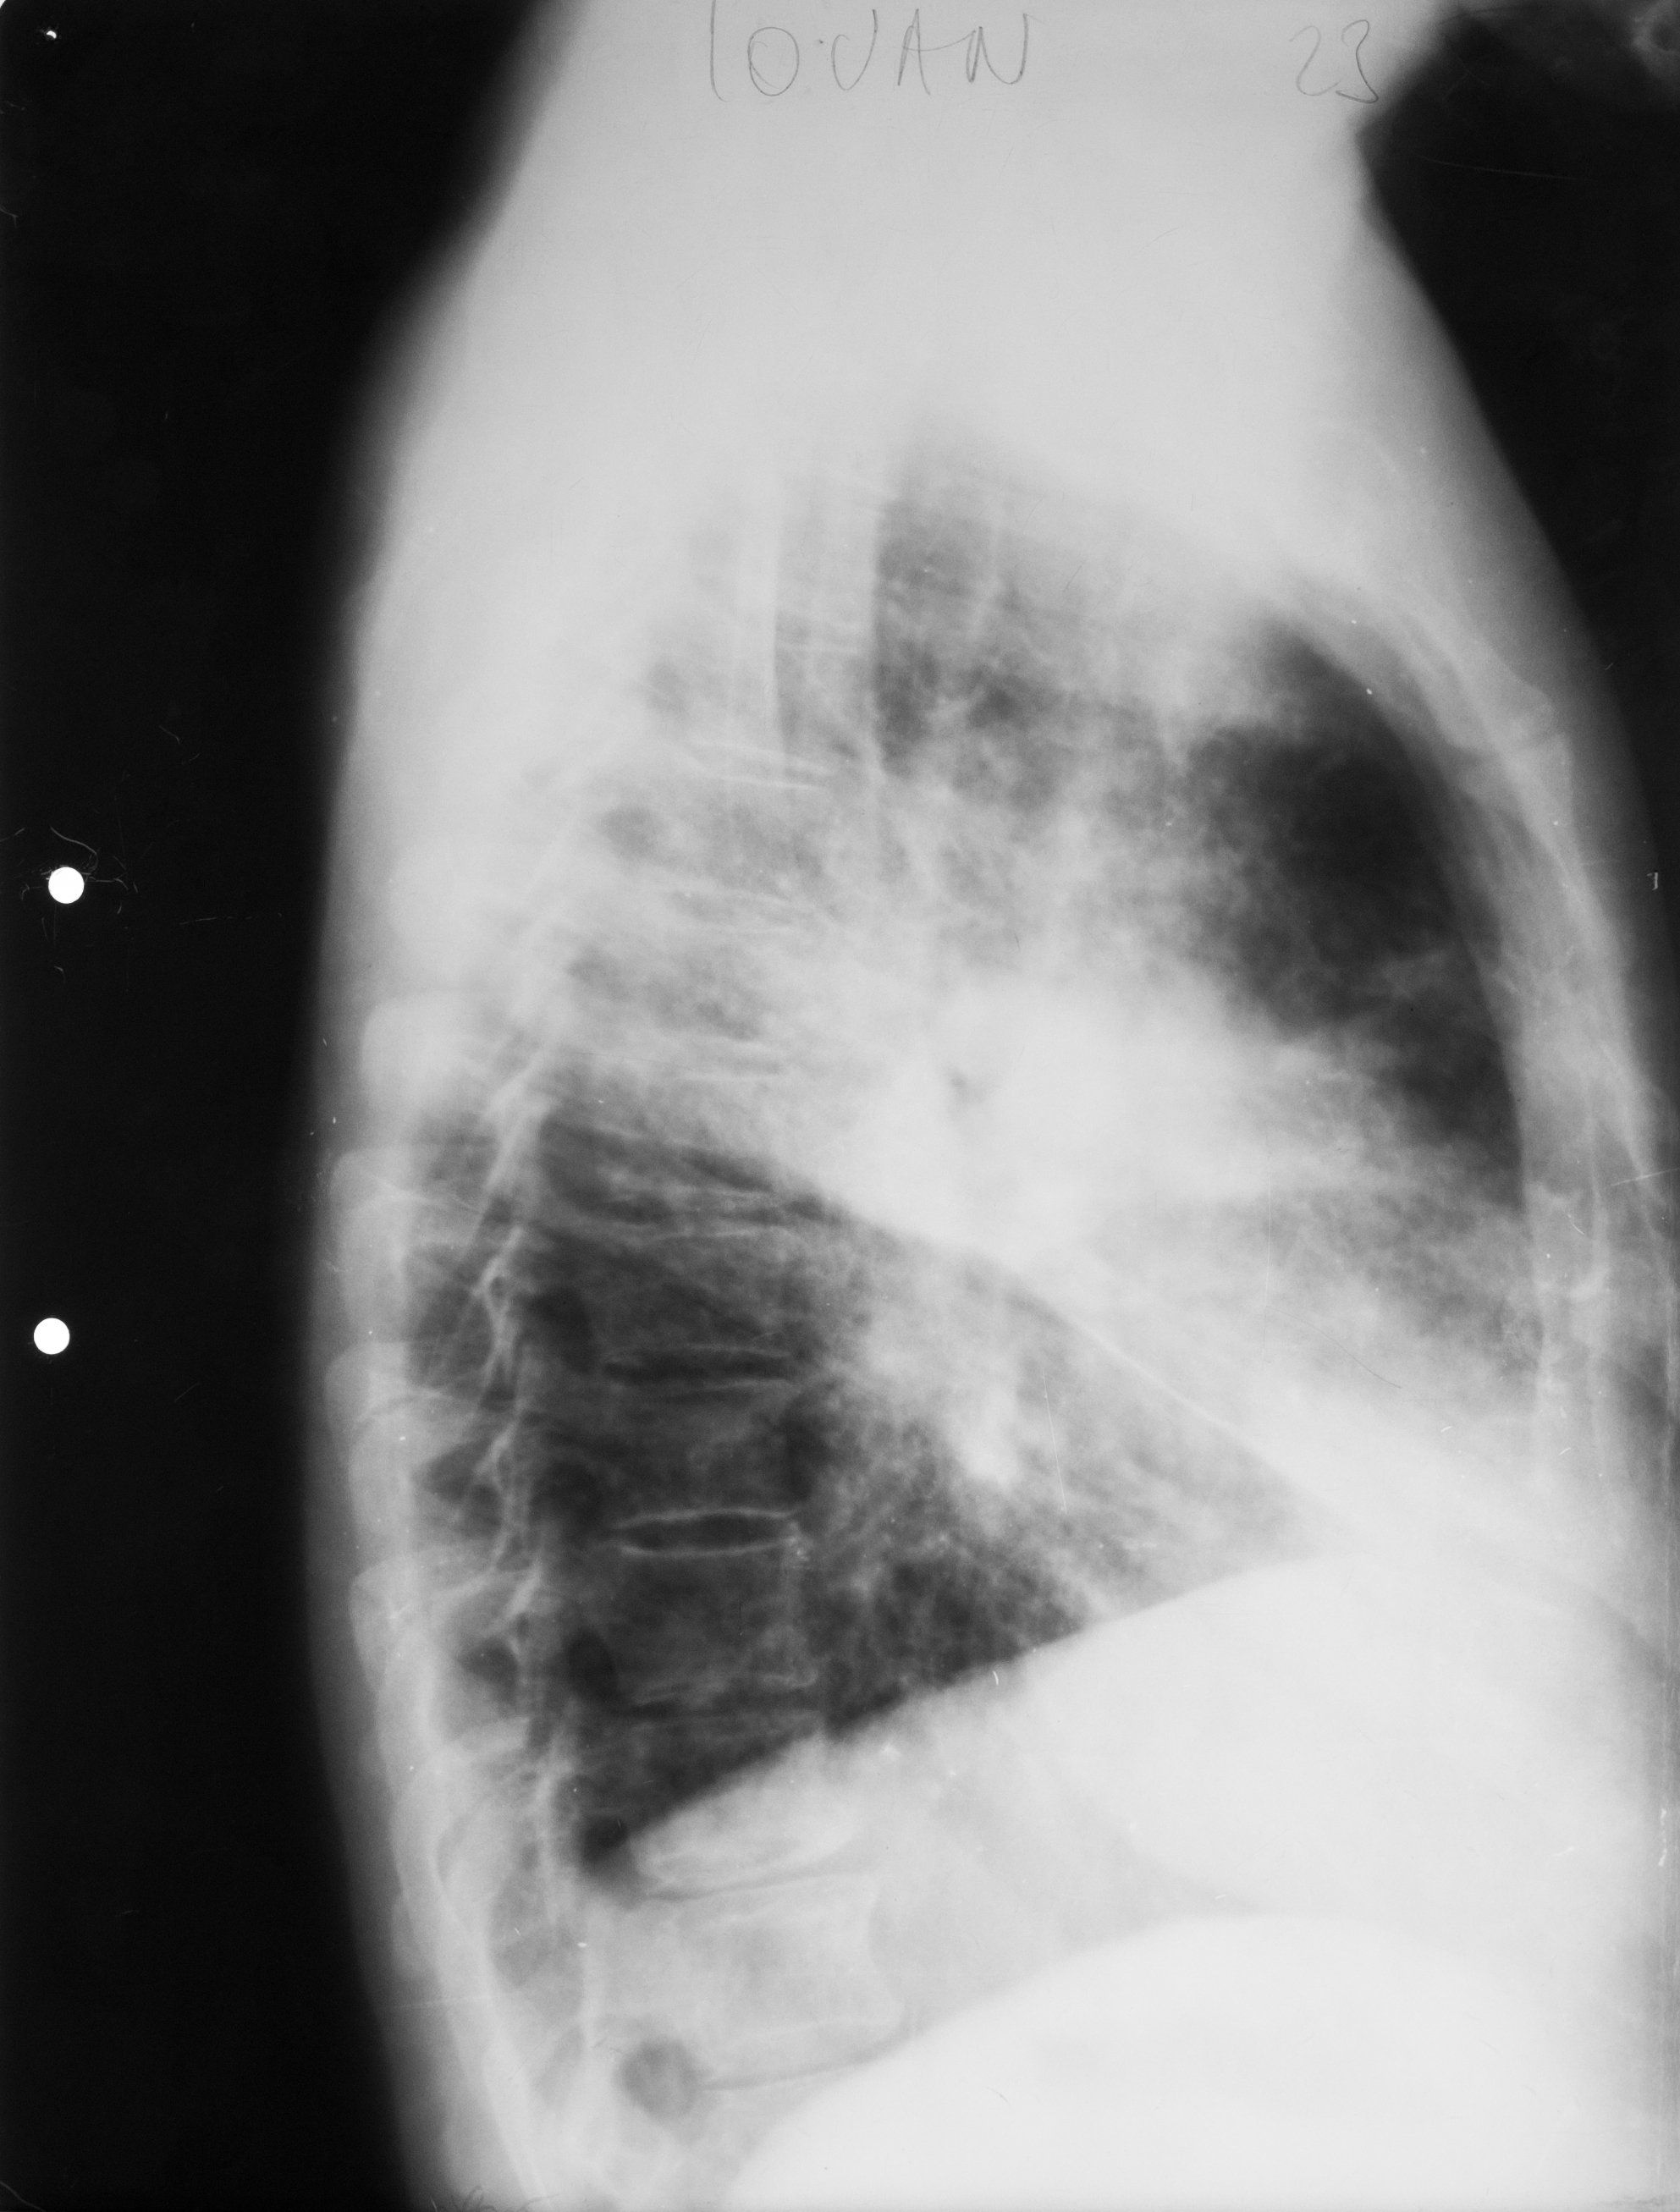

Rx toraco-mediastino-pleuro-pulmonar,de profil – opacitate